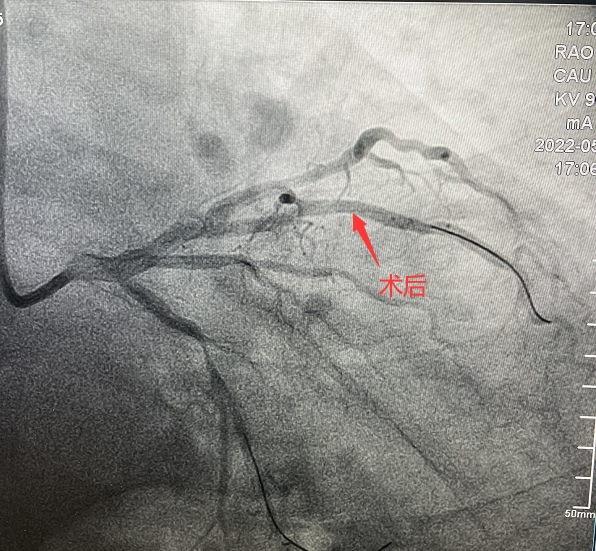

患者,51歲,男性,入院診斷為:冠心病、不穩(wěn)定型心絞痛。冠狀動(dòng)脈造影顯示對(duì)角支90%狹窄病變。對(duì)于該類患者,通過(guò)介入治療(PCI)方式早期干預(yù)相關(guān)血管可明顯減輕患者癥狀,減少死亡率、并發(fā)癥,改善患者的預(yù)后。在醫(yī)生與患者及家屬溝通時(shí),患者家屬提到,他們了解得知臨床有一種新型的可吸收支架,置入體內(nèi)后能完全被降解和吸收,患者及家屬希望能用這種新型的支架進(jìn)行手術(shù)治療。由于生物可吸收支架有著嚴(yán)格的適應(yīng)癥,因此經(jīng)過(guò)嚴(yán)格評(píng)估,最終對(duì)患者進(jìn)行了Xinsorb生物可吸收支架(BRS)置入術(shù)。支架植入術(shù)后,經(jīng)IVUS檢查,支架貼壁良好,結(jié)果完美,手術(shù)順利結(jié)束。

可吸收支架植入手術(shù)中

手術(shù)造影圖